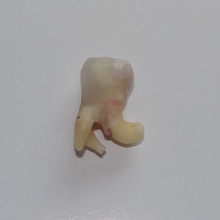

Trzykanałowa górna czwórka, nieczęsty przypadek.